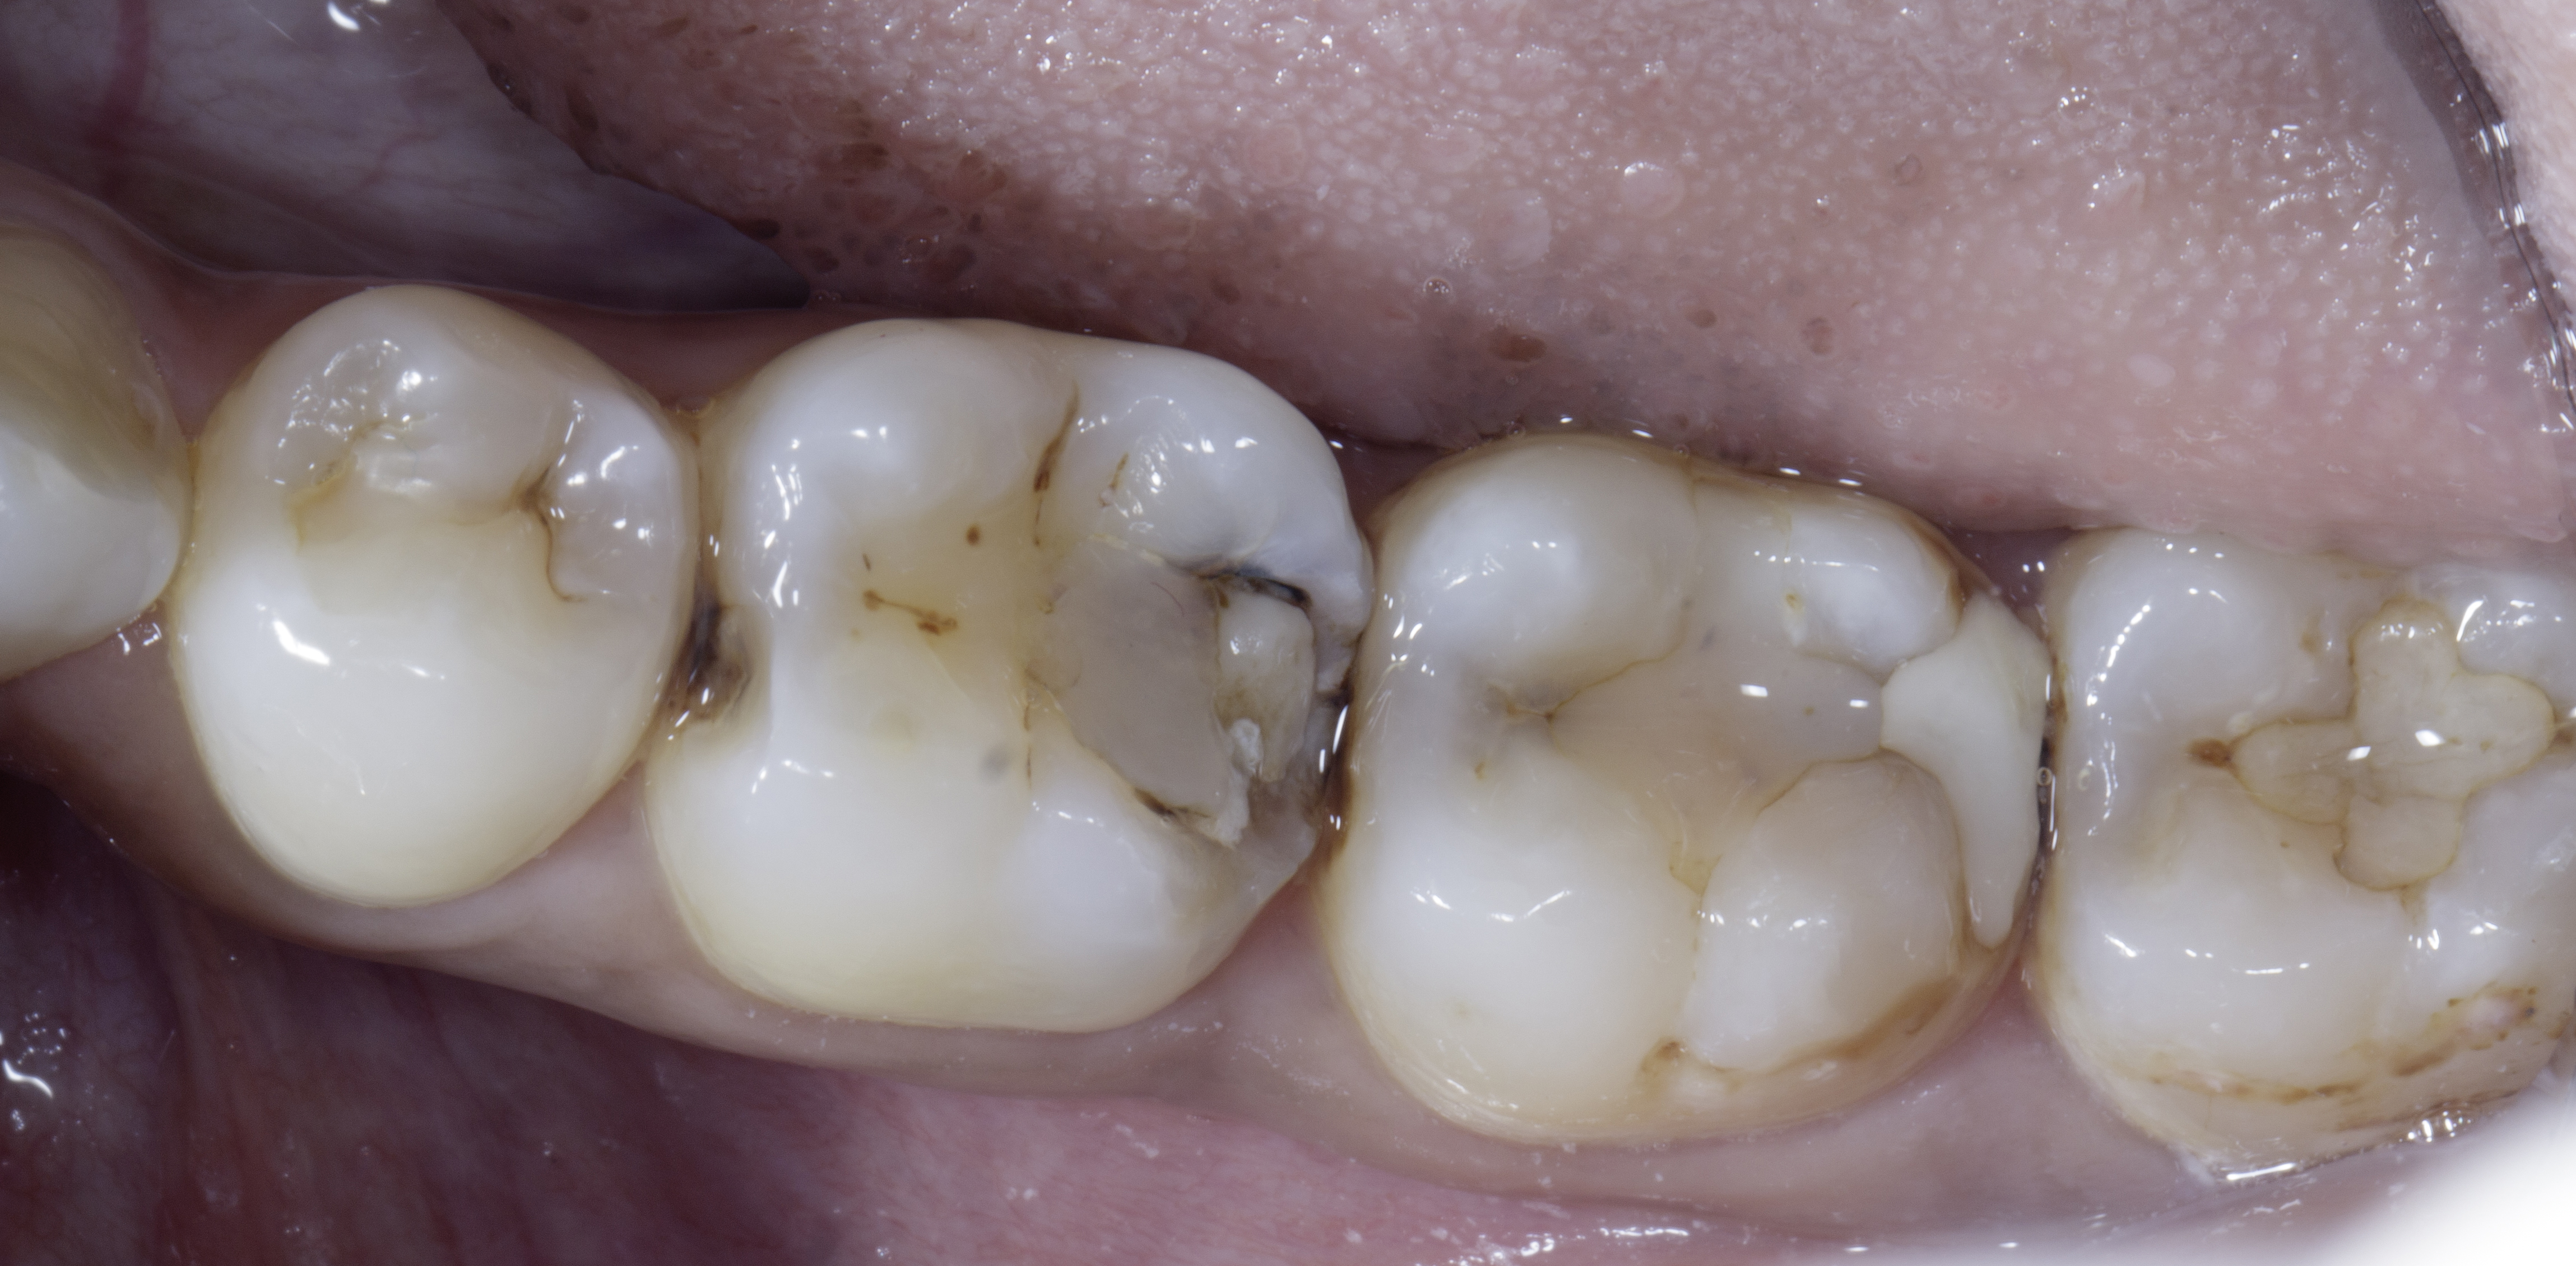

Rubber dam isolation was achieved using a wingless B1 clamp and heavy-gauge rubber dam to optimize the adhesive environment and enhance restoration longevity. Adequate isolation is critical for the success of any adhesive procedure.

Caries-disclosing dye was utilized to aid in complete removal of carious tissue and residual composite material in teeth #48, #47, and the distal surface of #46. Infected dentin was carefully excavated using a slow-speed round carbide bur. Establishing a well-defined peripheral seal zone, free from infected and affected dentin, was prioritized to ensure maximum bond strength.

On tooth #46, the distobuccal cusp was selectively reduced until sound, supported enamel and dentin were achieved. For tooth #48, a conservative tunnel preparation was performed on the mesial surface to preserve the integrity of the marginal ridge. All cavity preparations were subsequently refined using a superfine (yellow-band) diamond bur to remove unsupported enamel. Additionally, abrasive finishing discs were used to further eliminate any remaining unsupported enamel and to smoothen the cavity walls.

Figure 3

Figure 3.

The collage displays the prepared teeth after caries removal, addressed as follows:

- #48: Mesial tunnel preparation with an occlusal Class 1 defect.

- #47: Mesio-occluso-distal (MOD) defect preparation.

- #46: Class 2 defect preparation involving removal of unsupported enamel on the distobuccal cusp.

All preparations focused on removing caries, establishing a peripheral seal zone, eliminating unsupported enamel, and refining the proximal box.